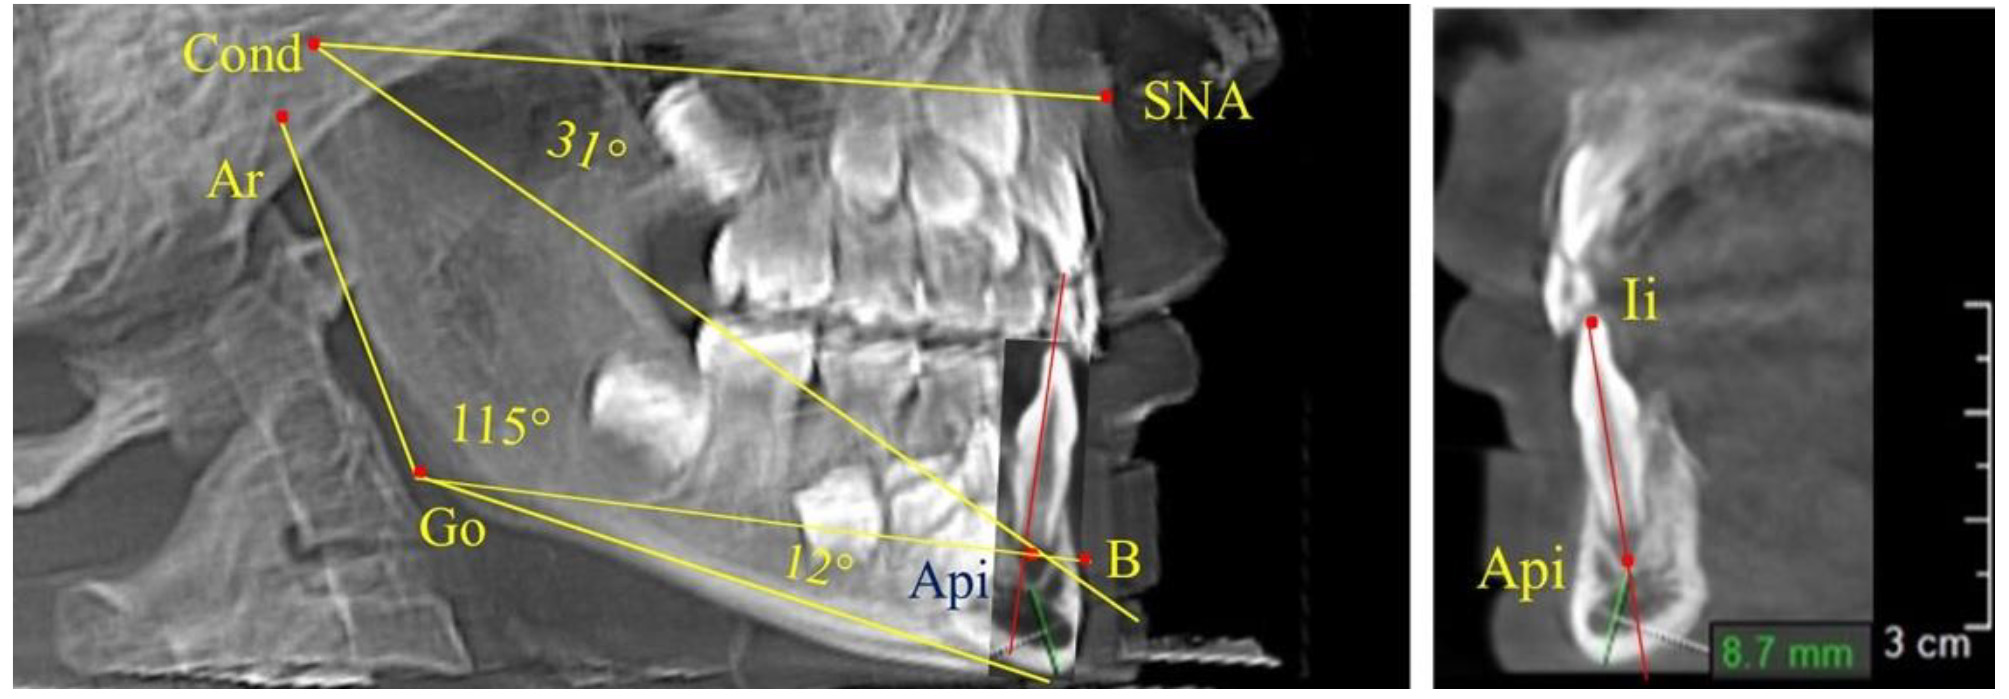

Линия, отделяющая гнатическую часть лица, соединяла верхнюю точку суставной головки Cond с точкой передней носовой ости SNA. Касательная к ветви нижней челюсти пересекали ее выпуклости, обозначаемые точками Ar и Т1. Касательную в телу нижней челюсти проводили от нижней точки подбородка Me, через выпуклость нижней части угла челюсти Т2. Место пересечения касательных линий определяло положение конструктивной точки Go.

Особое значение при анализе гнатической части лица уделяли нижнечелюстному резцовому сегменту. На режущем крае резца устанавливалась точка Ii (incisive inferior), а верхушку корня нижнего резца обозначали как Api (apicalе inferior).

Через апикальную точку нижнего резца от суставной точки проводили линию Cond-Api, которая с линией Cond-SNA образовывала угол гнатический части лица SNA-Cond-Api, используемый для оценки ее основных параметров.

Кроме того, угол нижней челюсти Ar-Go-Me линией Go-Api делили на две составляющие. Верхняя часть угла Ar-Go-Api определяла значение альвеолярного нижнечелюстного угла, а угол Api-Go-Me определял особенности части тела нижней челюсти (рис. 1).

Особенность анализа телерентгенограммы в периоде сменного прикуса заключалась в том, что наслоение зачатков постоянных зубов затрудняло определение апикальной точки нижнего резца. В подобных случаях использовали метод совмещенного анализа телерентгенограммы с фрагментом томограммы, на котором, также как и на телерентгенограмме, определяли положение резцовой и апикальной точек с построением условной вертикали, которая служила ориентиром для совмещения фрагментов (рис. 2).